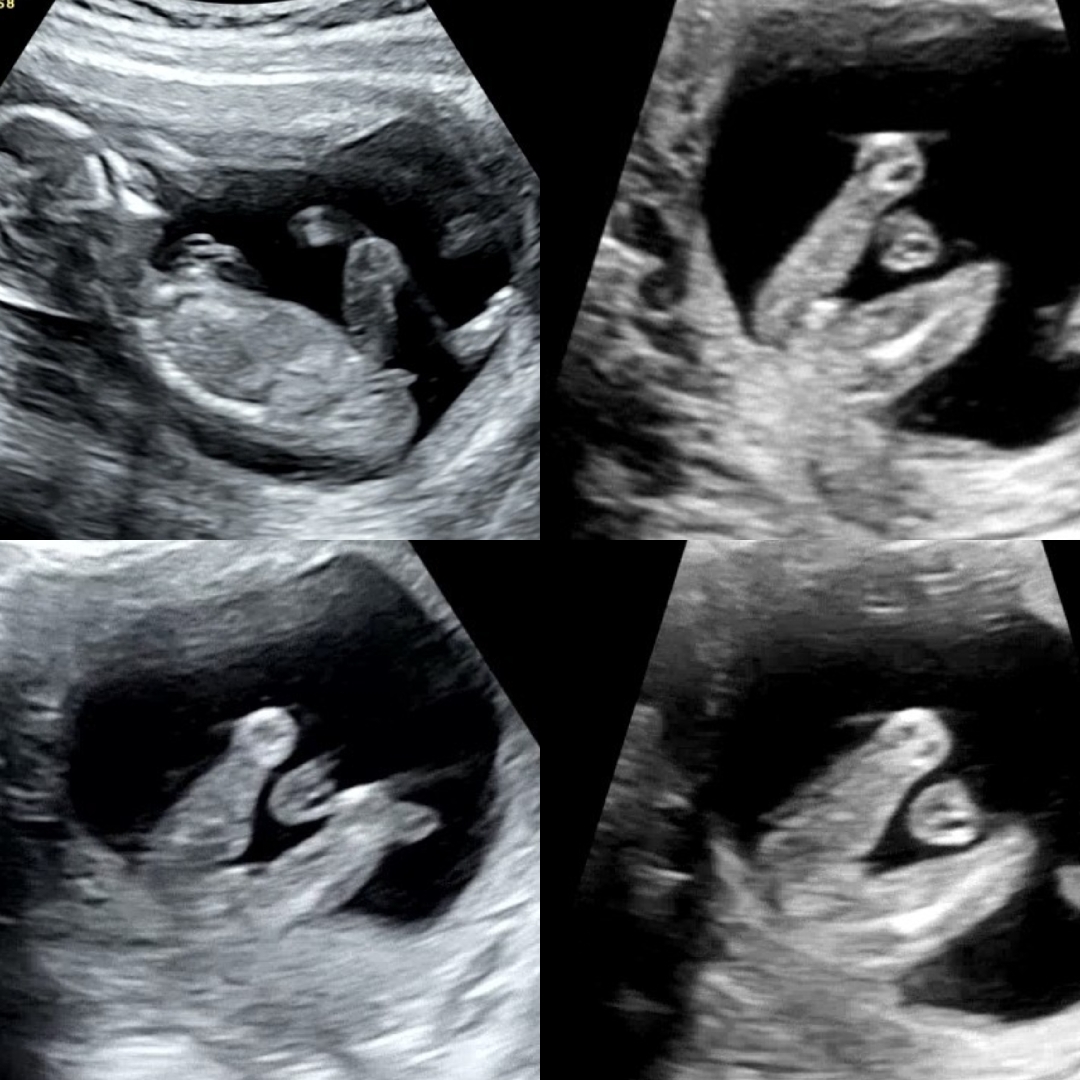

15주5일차 성별봐주세요ㅠㅠ

15주5일차 병원 두곳갔고 한곳은 딸인거같다 하셨는데 다른각도 보니 아들같기도 하다며 애매해서 말못하겠다 하셨고 다른 한곳은 아들인거 싶었는데 밑 각도에서 보니 딸에 가까운거같다고 애매하지만 딸6 아들4 정도 생각된다고 하시더라구요ㅠㅠㅠ 12주차영상 올렸었을때 ㅈㄲㅁ님 각도법은 딸이라고 하셨어요 도대체 성별이 뭘까용...!

각도가 생각보다 맞더라구용 아들에 한표요!!ㅋㅋ

전 아들같아요~~!2번사진보니 아들같은데요~~!!!🩷

전 왠지 딸같아요!

아들..?이아닐까요ㅎㅎ1번사진 넘아들같은데

1번 사진 봤을땐 아들같은데 다른각도에서 또 보면 아들정도는 아닌거같다고 딸일가같다거 하시는데 아무리 봐도 모르겠더라그요..